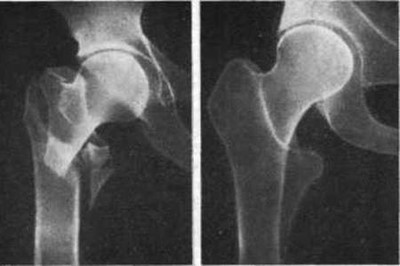

Это стоит обсудить с врачом. Он даст рекомендации в зависимости от тяжести перелома, возраста и сопутствующих заболеваний пациента. В большинстве случаев операция необходима, и, по международным рекомендациям, ее лучше всего провести в течение трех дней после травмы. При переломе шейки бедра проводят остеосинтез или эндопротезирование — полную или частичную замену тазобедренного сустава. При остеосинтезе хирурги используют стержни, винты и пластины, которые скрепляют перелом и помогают костям быстрее срастись. Если у врача есть опасения, что такая операция не позволит бедру хорошо зажить, особенно если пациент старшего возраста, — он порекомендует эндопротезирование.

При частичной замене хирург удаляет головку и шейку бедренной кости, а вместо них устанавливает протез. А при полной замене протез ставится еще и вместо гнезда тазобедренного сустава. Чтобы чуть лучше понять, как это выглядит и происходит, посмотрите на эту картинку.

Ниже рентгенограммы ложного сустава, асептического некроза, перелома шейки бедра и чрезвертельного перелома.

Из-за особенностей кровообращения шейка бедра как правило не срастается даже у молодых (исключение молодой возраст и вколоченный перелом), без оперативного вмешательства, то бишь эндопротезирования тазобедренного сустава, есть шанс "встать на ноги", если в столь преклонном возрасте не добьют осложнения, но это будет асептический некроз головки бедренной кости, образование ложного сустава, укорочение конечности, нога перестаёт быть опорной, поэтому до конца жизни ходьба на костылях/ходунках. А вот если сломаться чуть дистальнее (ниже), то чрезвертельные переломы уже намного охотнее срастаются.